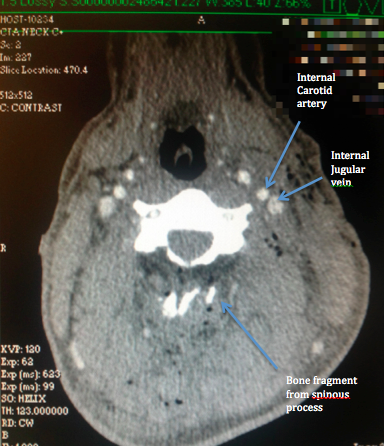

These next images show the path of the bullet through the neck, and the vital structures that the bullet somehow didn’t disrupt. Also included is an anatomy slide taken from the Internet, showing the gross structures at roughly the same level for comparison. In the first image, the path of the bullet can be seen by the small pockets of air drawn into the tissues as the bullet passed through, which appear black on the CT image. A blue line has been drawn along the bullet’s rough path to illustrate. The next image was taken after a dye was injected in the casualty’s veins, which pumped around his blood vessels, causing them to appear white on the CT scan.

Mentally superimposing the path of the bullet, it can be seen that it passes directly through a rather large pipe in the front of the casualty’s neck, which I assess as being the internal jugular vein. (I’m very happy to be corrected by any radiologists out there!) Immediately next to the internal jugular vein is an even more important structure, the internal carotid artery, which, had it been disrupted, would have almost certainly resulted in the death of the casualty given the circumstances on the day. Miraculously, neither of these major blood vessels were damaged, with the only rational explanation offered by the treating surgeon being that the bullet simply pushed them aside. Once again, in my opinion, were this to have been a M4 round, I suspect the outcome would have been dramatically worse.

So far I have only considered the damage done by the permanent cavity caused by the bullet, which both fractured the spinous process of the casualty’s vertebra and punched through the exact location of his major neck blood vessels without disrupting them. Of more medical significance, both on the day and ongoing since, was the damage done by the temporary cavitation of the bullet as it passed through. Those who have read my previous post (or have a good grasp of the subject) can disregard the following video, but for those who haven’t, the following YouTube video by Brass Fetcher demonstrates the pressure wave generated by a 7.62x39mm bullet when it passes through tissue. In the video, a bullet is shot into ballistic gelatin that has roughly the same density as human tissue. The pressure wave seen disrupting the gelatin in the video is caused as the bullet rapidly decelerates and transmits energy into the gelatin. The same occurs in human tissue with the pressure wave, or temporary cavity, causing damage to structures around, but not in the direct path of, the bullet.